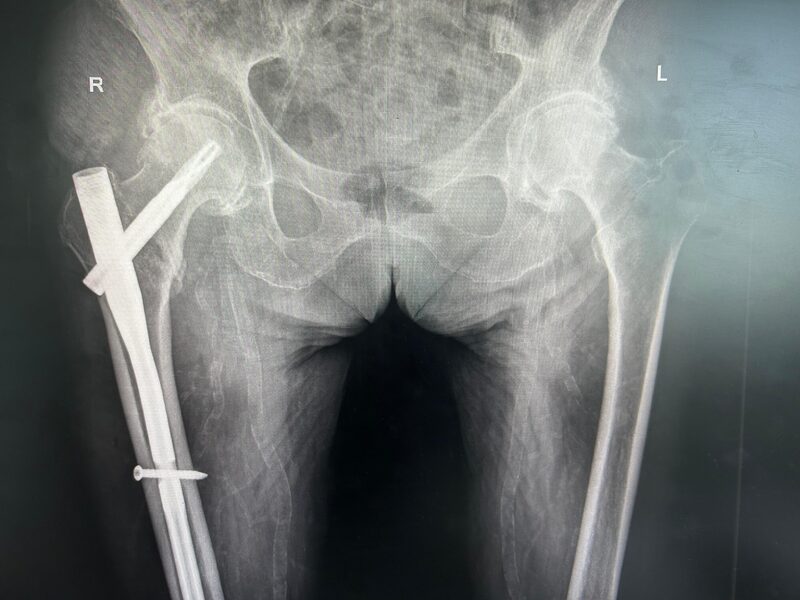

алуга замена сустава

Калуга замена сустава 103 фотографий